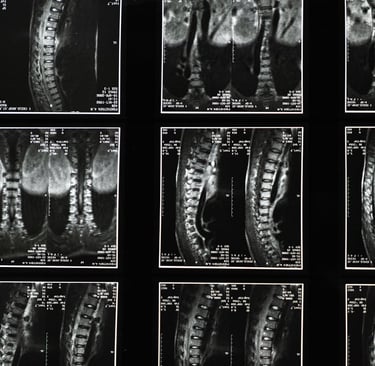

L’IRM lombaire (Imagerie par Résonance Magnétique) est un examen médical permettant d’explorer en détail la colonne vertébrale, les disques intervertébraux et les racines nerveuses. Cet examen est souvent demandé lorsqu’un patient présente une lombalgie persistante, une sciatique ou une suspicion de hernie discale lombaire.

Que montre une IRM lombaire ?

L’IRM lombaire permet d’observer avec précision :

les disques intervertébraux

les racines nerveuses

la moelle épinière

les articulations de la colonne vertébrale.

Cet examen est particulièrement utile pour diagnostiquer :

une hernie discale

un canal lombaire étroit

certaines pathologies inflammatoires ou dégénératives de la colonne vertébrale.